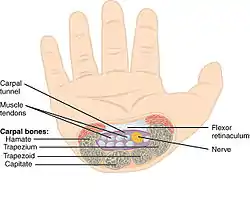

The tunnel is bounded by the bones of the wrist and flexor retinaculum from connective tissue. Normally several tendons from the flexor group of forearm muscles and the median nerve pass through it. There are described cases of variable median artery occurrence.

Structure

The carpal bones that make up the wrist form an arch which is convex on the dorsal side of the hand and concave on the palmar side. The groove on the palmar side, the sulcus carpi, is covered by the flexor retinaculum, a sheath of tough connective tissue, thus forming the carpal tunnel. On the side of the radius, the flexor retinaculum is attached to the scaphoid bone, more precisely its tubercle, as well as the ridge of trapezium. On the ulnar side, it is attached to the pisiform and hook of hamate.[4]

The narrowest section of the tunnel is located a centimetre beyond the mid-line of the distal row of carpal bones where the sectional area is limited to 1.6 cm2.[2]

Ten structures pass through the carpal tunnel, most of them flexor tendons[2] (not the muscles themselves):

- flexor digitorum profundus (four tendons)

- flexor digitorum superficialis (four tendons)

- flexor pollicis longus (one tendon)

- Median nerve between tendons of flexor digitorum profundus and flexor digitorum superficialis